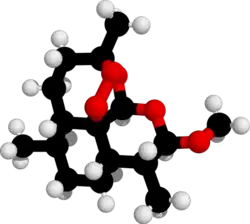

| Formula | C16H26O5 |

| 3D model (JSmol) | |

Artemether is a methyl ether derivative of artemisinin, which is a peroxide-containing lactone isolated from the antimalarial plant Artemisia annua. It is also known as dihydroartemisinin methyl ether, but its correct chemical nomenclature is (+)-(3α,5aβ,6β,8aβ,9α,12β,12aR)-decahydro-10-methoxy-3,6,9-trimethyl-3,12-epoxy-12H-pyrano[4,3-j]-1,2-benzodioxepine. It is a relatively lipophilic and unstable drug,[20] which acts by creating reactive free radicals in addition to affecting the membrane transport system of the plasmodium organism.[13]